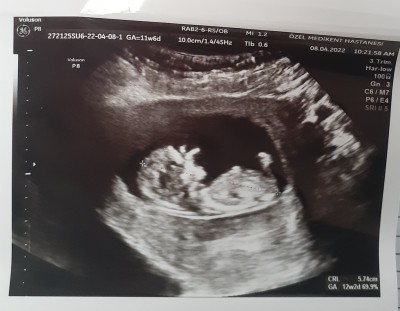

Tahminde lutfen cinsiyet nedir

Tahminde bulunurmusunuz

Kız bebek diyorum. Kaçıncı hafta ultrasonu bu ?